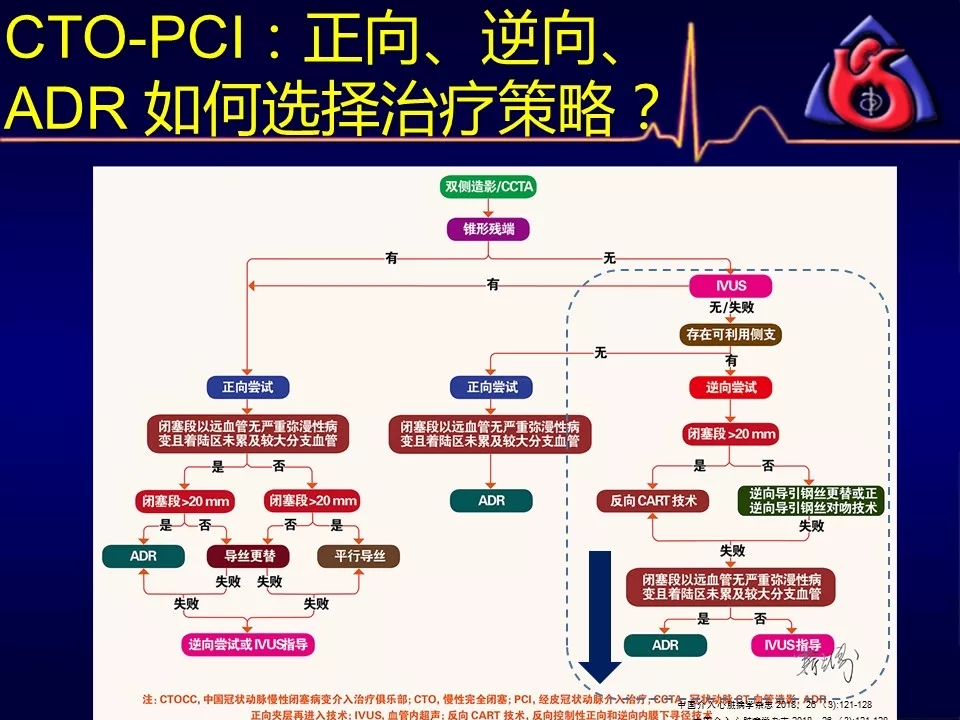

如何选择正向、逆向、IVUS指引及ADR技术?